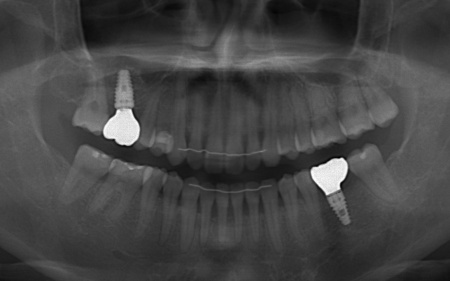

矯正がある程度進んだ段階で、右上と左下のインプラント手術を実施しました。

その際、右上の奥歯は鼻の奥にある空洞(上顎洞)に近く骨の厚みが不足していたため、上顎洞の粘膜を押し上げた部分に人工骨を入れて骨を増やすソケットリフトを併用しています。

一方、左下の奥歯は頬側(外側)の骨が薄かったため人工骨を入れて骨量を補うGBR(骨再生誘導法)を施しました。